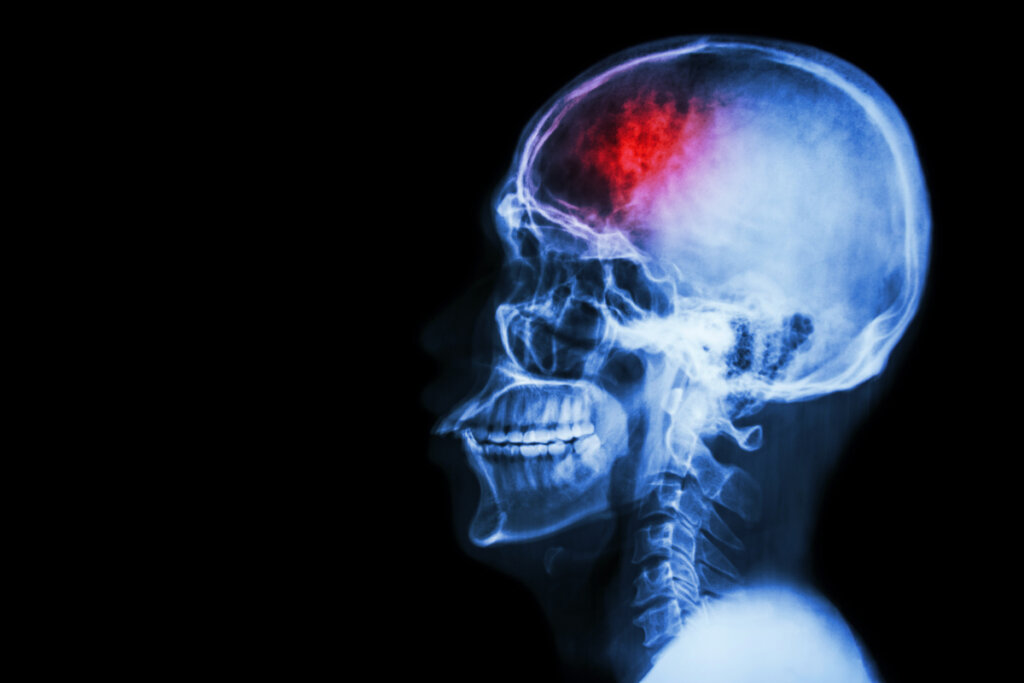

A disfunção executiva não é um distúrbio em si, mas um déficit que pode aparecer em diferentes condições. Tenhamos em mente que, a nível neurobiológico, a função executiva está diretamente associada ao córtex pré-frontal. Essa região do cérebro se desenvolve principalmente durante a infância e a adolescência, sendo nessas fases que os menores progridem e aperfeiçoam essas habilidades.

Esse déficit executivo também pode aparecer como parte de um transtorno de ansiedade, depressão e outras condições psiquiátricas. E é especialmente relevante no caso da doença de Alzheimer e outras demências, uma vez que chega a comprometer a autonomia e a segurança do idoso. Por outro lado, também pode surgir como resultado de danos cerebrais causados por traumas ou outras lesões.